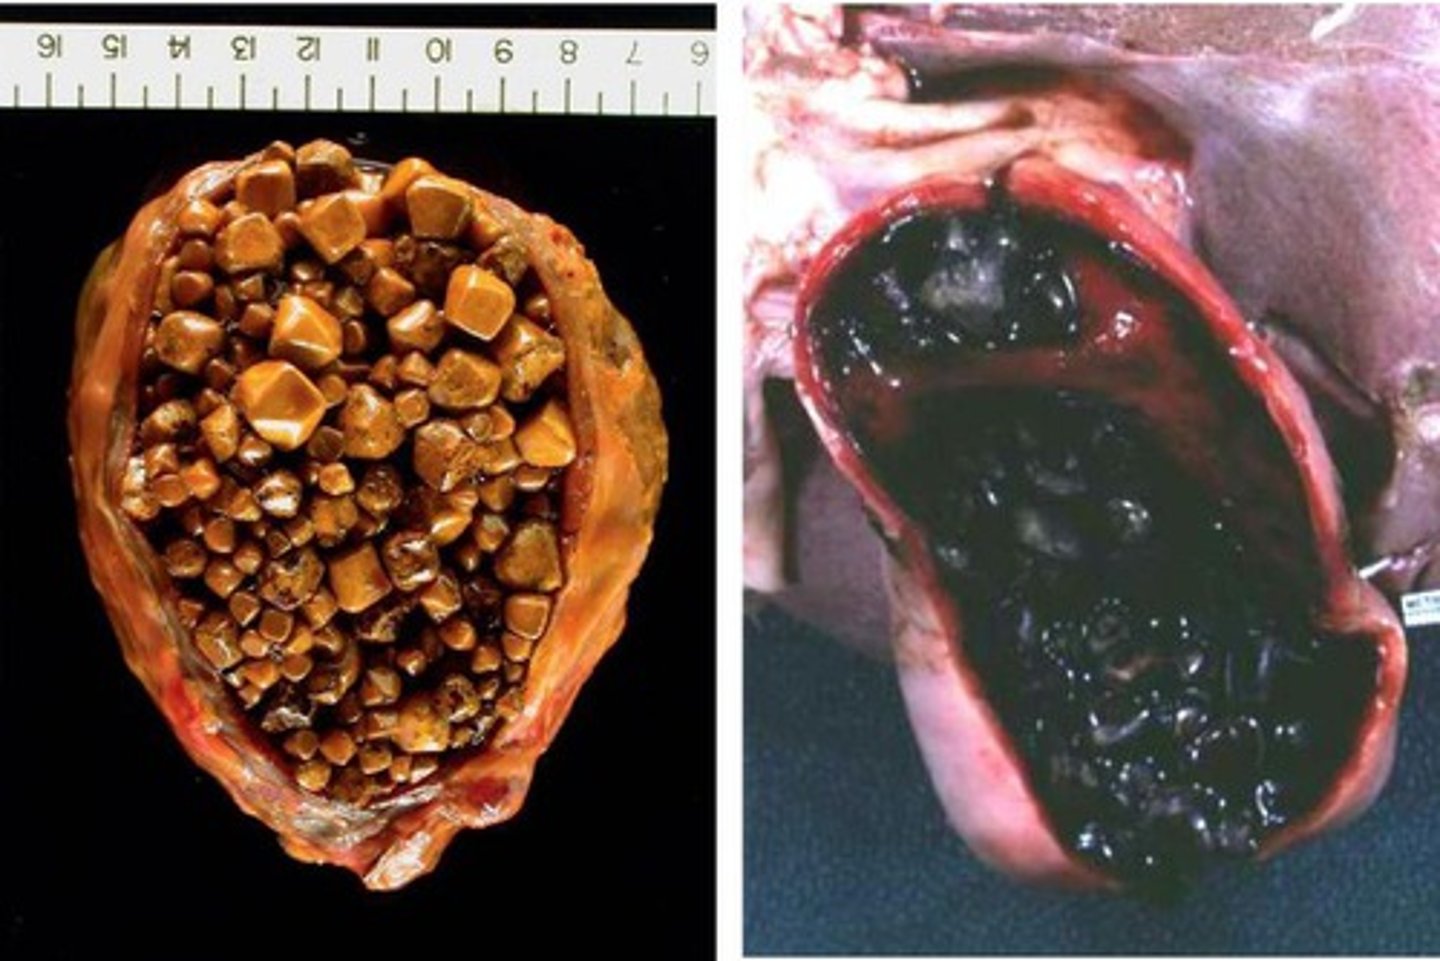

Cholelithiasis (CHOLESTEROL Gallstones)

Define Condition:

Yellow/Yellow-brown stones in gallbladder

Cholelithiasis (PIGMENT Gallstones)

Define Condition:

Stones from UCB in bile (insoluble in H2O)

Black Stones

-Path: Chronic Hemolysis (HS and SCD = RBC Turnover)

> Increased UCB --> Calcium Bilirubinate

> RADIOPAQUE d/t Calcium

Brown Stones

-Hx:

> E. coli

> Clonorchis sinensis

-Path: Infection

> Increased Beta-glucuronidase --> converts CB to UCB ==> Calcium Bilirubinate + Increased FAs

-Dx: Imaging

> RADIOLUCENT (Calcium SOAPS)